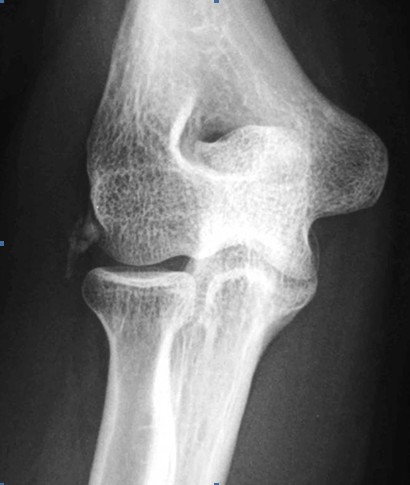

The diagnosis of tennis elbow is usually made by history and clinical examination. X-rays are not always necessary but occasionally may show pathologies such as focal calcification at the common extensor tendon origin.